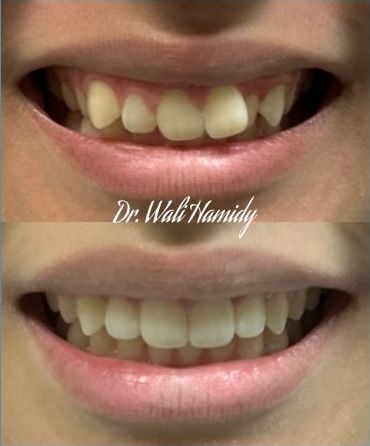

Check out our Invisalign® treatment gallery to see how this orthodontic service can straighten your teeth and improve your smile. Contact La Jolla Dental Image at 858-202-0481 today to make an appointment with our dentist, Dr. Wali Hamidy, and learn more about Invisalign clear aligners in La Jolla, California.